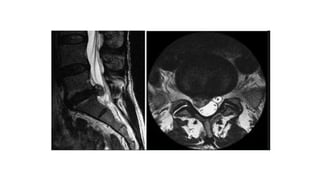

 Chụp cộng hưởng từ (MRI): hình hình ảnh trực tiếp của TVĐĐ

4. Chẩn đoánthoát vị đĩa đệm 4.1. Chẩn đoán xác định 4.1.2.Chẩn đoán cận lâm sàng  Chụp cộng hưởng từ (MRI): hình hình ảnh trực tiếp của TVĐĐ  Phương pháp chụp cắt lớp vi tính đĩa đệm: độ nhậy và độ đặc hiệu không cao trong chẩn đoán TVĐĐ.  Phương pháp chụp đĩa đệm (discography): hình ảnh trực tiếp về nhân nhầy của đĩa đệm.  Phương pháp chụp khoang ngoài màng cứng phía trước: hình ảnh gián tiếp đĩa đệm TV  Phương pháp chụp tĩnh mạch gai sống thắt lưng: => gián tiếp thấy hình ảnh đĩa đệm bị thoát vị.